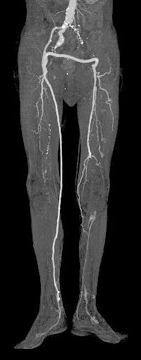

この言葉の意味は書いて字のごとく四肢(殆どは下肢)を救うということです。閉塞性動脈硬化症が進行し安静時疼痛(FontaineIII度)や虚血性潰瘍(FontaineIV度)を発症するような重症虚血肢の状態から下肢を日常生活に障害のない状態に戻す治療を指します。われわれは日常の社会生活において下肢を切断した人々をあまり意識することはありません。

しかし医学が発達したと思われている現代においても閉塞性動脈硬化症やビュルガー病など下肢血流障害によって現実に下肢を切断されている人々が少なからず存在します。この様な病気に対してわれわれ血管外科医は治療法を研究模索してきました。

その結果、以前では切断しか方法が無かったような状態の足を救肢できる可能性が増えてきました。具体的には血管拡張剤の開発、血管内治療(ステント)の発達、血行再建術(バイパス手術)手技の向上、遺伝子治療などの開発です。しかしまだ膝より下の下腿血流障害に対しては予後が悪く、切断されている例が多いようです。

当科では下肢の血行再建術(バイパス術)、特に下腿への血行再建術(バイパス術)に積極的に取り組み、大腿・下腿切断と診断された患者さんの下肢を切断せずに済む状態か、切断が必要な場合でもできるだけ足趾切断のみで済ませ、義足・装具を必要としない社会生活への復帰を目指しています。

実際には平成15年1月から現在までにFontaineIII度・IV度の患者さん21例に対し、下肢・下腿への血行再建術(バイパス術)を行った結果11例を切断不要な状態に、8例を足趾切断のみで義足・装具を必要としない社会生活への復帰を可能にしました。